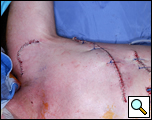

Eleven months later, he presented with a several month history of a painful fixed, firm mass over the pectoral area of the left chest and a smaller mass inferior to this (Figure 1). CT scan demonstrated a new 2 cm nodule in the left upper lobe associated with an anterior chest wall mass six centimeters in size in addition to bilateral new pulmonary nodules (Figure 2). The mass was tethered to the skin and in danger of eroding through it. The patient underwent en-bloc resection of the chest wall and adjacent lung (Figures 3a-c). The resulting defect (Figure 4a) was reconstructed with 2 mm Gore-Tex patch (Figure 4b) and pectoralis major muscle flap (Figure 4c) with primary skin closure (Figure 4d). The pathology revealed metastatic chordoma (Figures 5a-d). The patient recovered well, leaving the hospital on the sixth postoperative day.

Twelve months postoperatively, the patient experienced recurrence of his disease in the chest wall, but has had good palliation from the initial chest wall involvement. He has otherwise felt well and has good use of his left upper extremity (Figure 6a, 6b, 7).